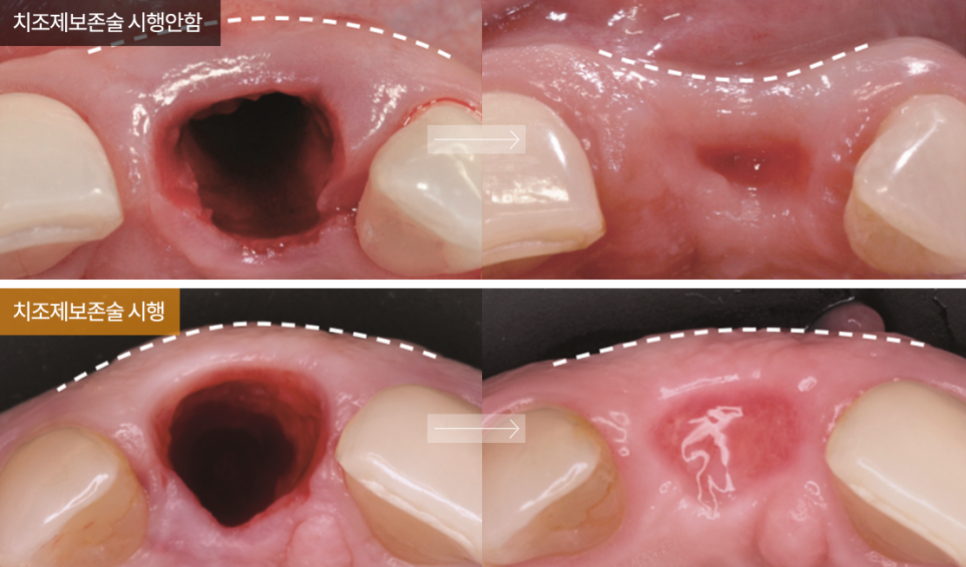

치주조직손상 원인

임플란트 보철 부작용이나 수술 부작용의 경우 환자의 부주의가 큰 원인으로 꼽히지만, 치주 조직 손상의 원인은 치주 조직 재생을 소홀히 한 의료진의 원인이 크다고 할 수 있겠습니다. 치아 발치 후 36개월 내에 34mm 정도의 잇몸과 잇몸 뼈의 퇴축이 발생하는데요, 치주 조직 손상으로 인한 부작용인 임플란트 탈락, 잇몸 들림, 금속 노출 등의 위험을 줄이려면 발치 후 치주 조직 재생을 극대화해야만 합니다.

강남새로치과에서는

임플란트 식립을 동반한 외측동저 거상 시 연어주사가 상처재생을 촉진시킨다는 논문 자료를 기초로 연어주사 임플란트를 최초 시행한 정재욱 대표원장만의 타 병원 대비 월등한 실력으로 치조제보존술을 시행하여 치주 조직인 잇몸과 잇몸 뼈의 유지 및 복원 효과를 최대한으로 끌어올립니다.

연어주사 시술 시 잇몸 치유 속도를 2배 가까이 촉진시켜 수술 기간을 단축시키는 것은 물론 치주 조직 손상으로 인한 부작용 위험의 스트레스를 덜어드립니다.